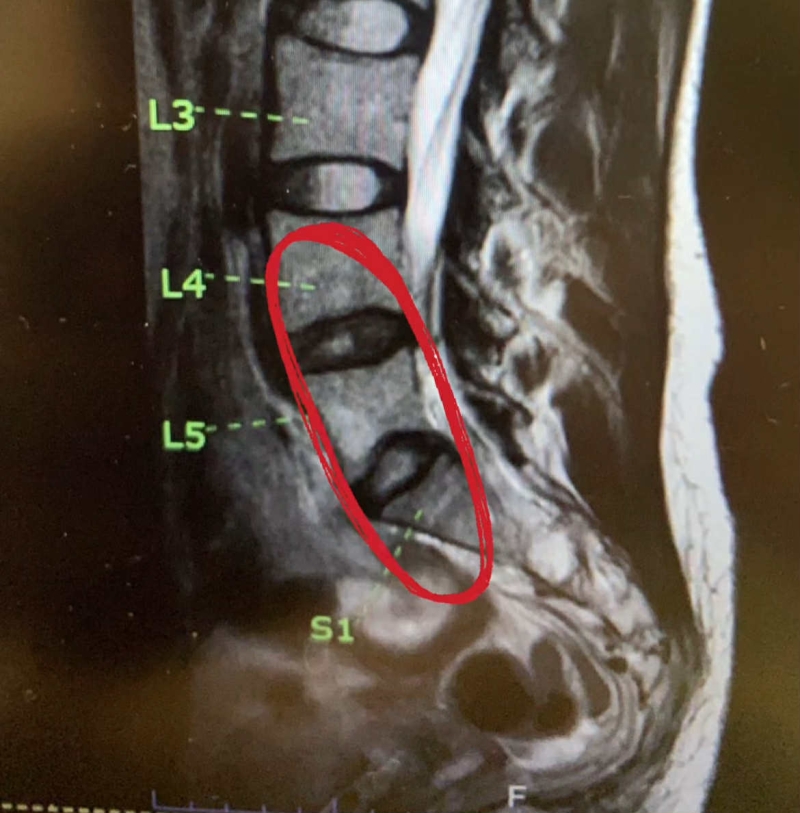

ล่าสุด เธอ ได้แชร์ภาพเอ็กซเรย์ผ่านอินสตาแกรม @newclear_hansa พร้อมเขียนว่า เจ้านี้ คือที่เสื่อม สีขาวๆ ตรงกลางแทบไม่เหลือ ทำให้ปวดหลังบ่อยๆ ค่า เรียกความห่วงใยจากแฟน ๆ ทันที

อีกทั้ง เจ้าตัว ยังระบุว่า ไม่ต้องเป็นห่วง ไม่ต้องมาเยี่ยมนะคะ พรุ่งนี้ก็กลับบ้านได้แล้ว หมอนรองกระดูกเสื่อม แต่ไม่ทับเส้นประสาท ยังโชคดี หมอบอกเป็นไปตามวัย